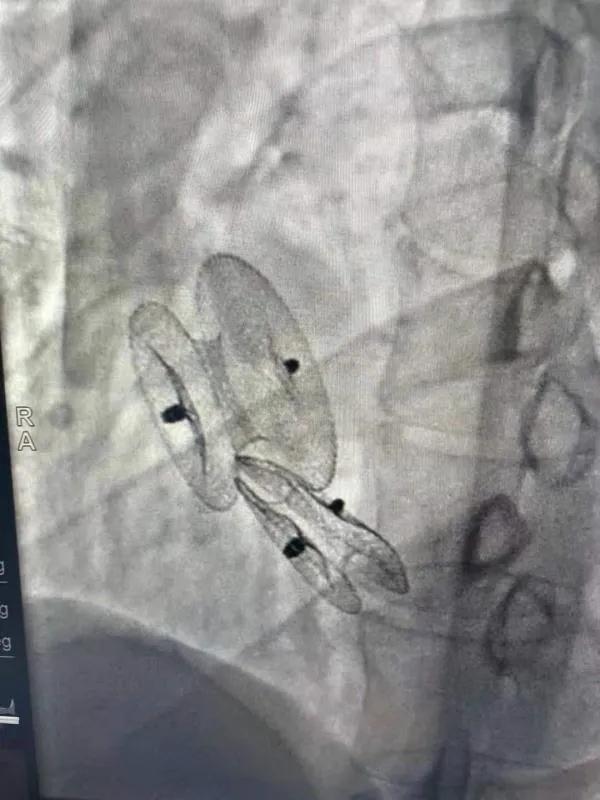

先天性心臟病房間隔缺損呈多孔型怎么辦?患者并非只能選擇開(kāi)胸手術(shù)。近日,西安國(guó)際醫(yī)學(xué)中心醫(yī)院心臟病醫(yī)院成功開(kāi)展一例雙孔房間隔缺損雙傘介入封堵術(shù)。

房間隔缺損是先天性心臟病的一種,介入手術(shù)相較于傳統(tǒng)的外科手術(shù)損傷小,風(fēng)險(xiǎn)相對(duì)較低,術(shù)后恢復(fù)快。一般的房間隔缺損多呈單孔,封堵難度較小,而雙孔房間隔的封堵難度大大增加,至今僅有國(guó)內(nèi)頂尖的封堵專(zhuān)家成功完成了數(shù)例而已。

患者是位27歲的年輕女性,經(jīng)常感到心慌,心臟超聲發(fā)現(xiàn)房間隔缺損,并且房間隔缺損呈雙孔型,大的約14mm,小的約9mm,兩個(gè)缺損間相隔較遠(yuǎn),介入封堵難度非常大。

在詳細(xì)了解患者病情,仔細(xì)閱讀患者影像資料后,曾廣偉主任已經(jīng)有了清晰的手術(shù)策略。在精心的準(zhǔn)備和團(tuán)隊(duì)的配合下,曾主任順利的利用兩個(gè)封堵器對(duì)房缺進(jìn)行了封堵。